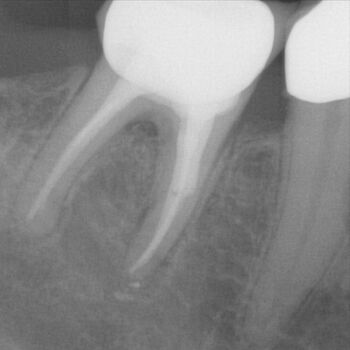

Fall 4: großer interradikulärer Entzündungsherd

Endodontie Fall 4: großer interradikulärer Entzündungsherd

Vor der Behandlung

Kontrolle nach Wurzelfüllung